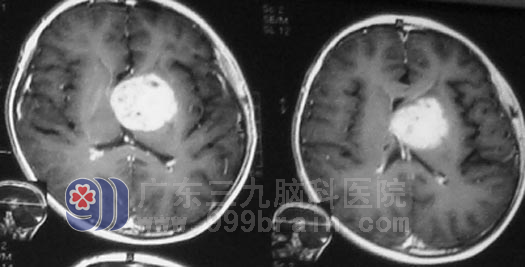

小勇住进了广东三九脑科医院神经肿瘤外科,影像学检查发现颅内肿瘤约3cm*2cm大小。考虑到小勇头痛严重,颅内压力较高,立即行脑室腹腔分流加三脑室占位活检术,术后小勇头痛很快缓解,病理结果为生殖细胞瘤。

▲放疗前